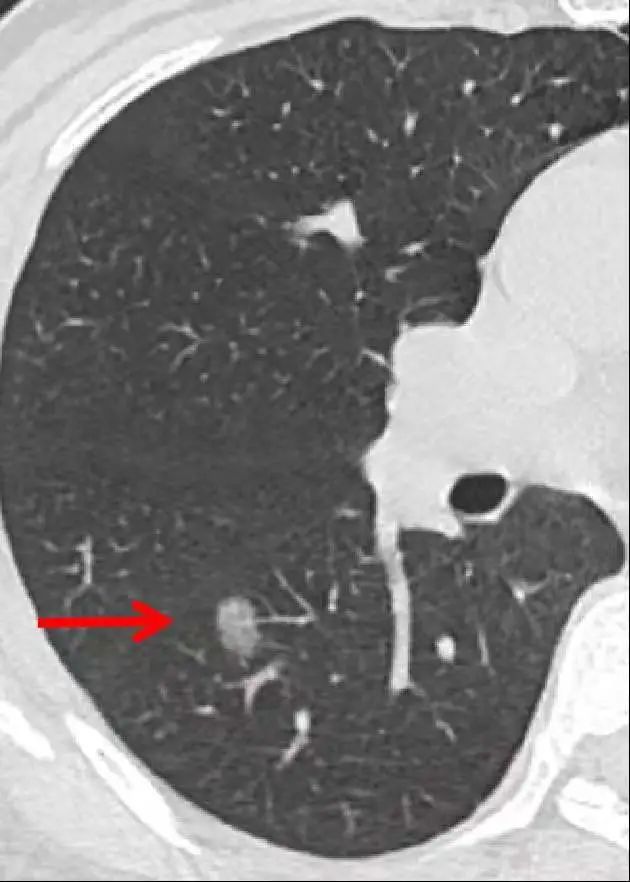

肺结节,影像学表现为长径≤3 cm的局灶性、类圆形、密度增高的实性或亚实性肺部阴影,可为孤立性或多发性,不伴肺不张、肺门淋巴结肿大和胸腔积液。

小于5mm的被称为微小结节,绝大部分是良性的;5-10mm的被称为小结节,需进一步评估及随访;当结节大于10mm的时候,恶性几率有所增高,要及时进一步检査诊断。

要分清是纯磨玻璃样肺结节、混合性磨玻璃样肺结节、还是实性肺结节。磨玻璃样肺结节的早期肺癌概率高于实性肺结节,混杂磨玻璃结节肿瘤概率高于纯磨玻璃结节。

有时还通过钙化形态判断结节性质,有4种良性钙化类型,分别为中央型、弥漫型、层状和爆米花样(图1)。中央型、弥漫型和层状钙化常见于有既往感染时,特别是组织胞浆菌病或结核病。爆米花样钙化是错构瘤(良性)中软骨样钙化的特征性表现(图2)。边缘光滑的结节内存在脂肪(CT值为-40至-120Hu)是肺错构瘤的可靠指标(图3)。

实性结节的生长速度是指直径增加2mm,对于亚实性结节可通过实性成分出现或增大来确定生长。大部分恶性结节的倍增时间为20-400天,典型类癌和浸润前病变(AIS和MIA)的倍增时间更长(>400)。因此,短期内(<20天)体积增大的结节或CT显示长期(>2年)保持稳定的结节很可能是良性病变。